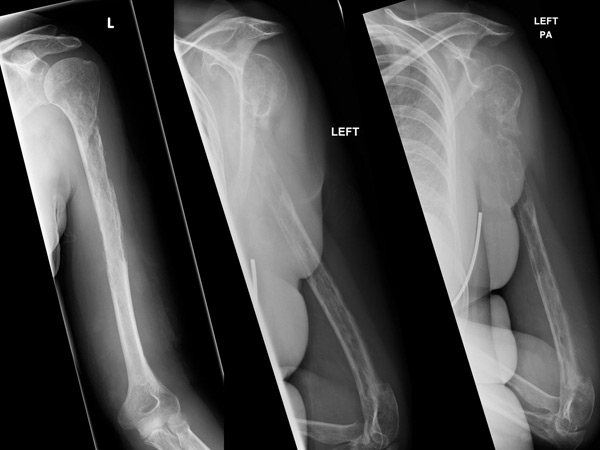

5. எலும்பு புற்றுநோய்

எலும்புகள்தான் ஒரு மனிதனுக்கு அதிக பலத்தை தருகிறது. நமது உடலில் எலும்புகள் இல்லையென்றால் நம்மால் எந்தவித செயல்களும் செய்ய இயலாது. இந்த வகை புற்றுநோய், எலும்பு மஞ்சையில் உருவாகி நாளடைவில் பெரிய ஆபத்தை தரும். அத்துடன் தசைகளின் வலுவை குறைக்க செய்யும்.